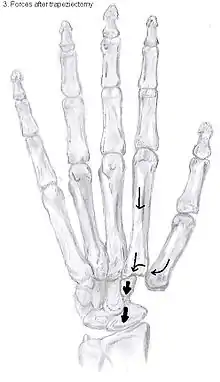

Trapeziectomy

During trapeziectomy[30], the trapezium bone is removed without any further surgical adjustments.The trapezium bone is removed through an approximately three centimeter long incision along the lateral side of the thumb. To preserve surrounding structures, the trapezium bone is removed "by splitting" it into pieces.

An empty gap is left by the trapeziectomy and the wound is closed with sutures. Despite this gap, no significant changes in function of the thumb are reported.[27] After the surgery, the thumb will be immobilized with a cast.

Trapeziectomy with TI

Some physicians still believe that it is better to fill the gap left by the trapeziectomy. They assume that filling the gap with a part of a tendon is preferable in terms of function, stability and position of the thumb. They are afraid that leaving a gap might result in complications such as shortening or subluxation of the thumb.